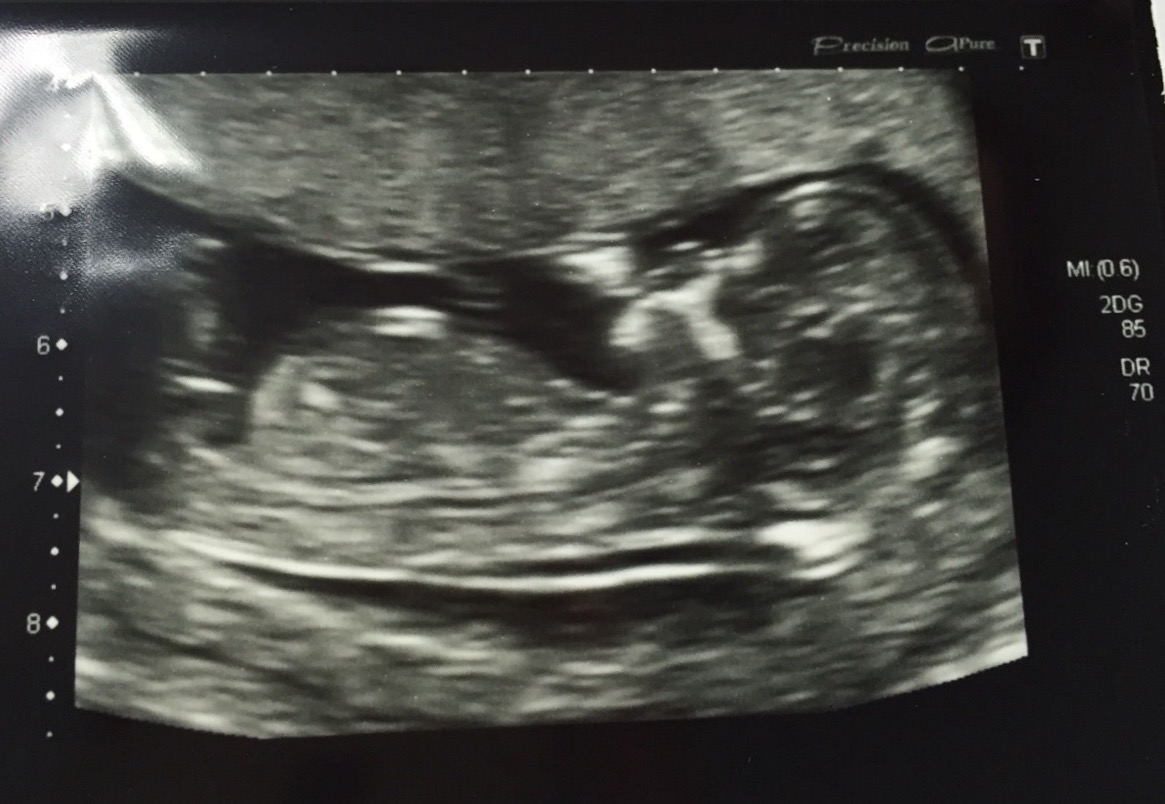

Please could you take a look at this scan measuring 13 weeks exactly, this is my new niece or nephew (sucking their little thumb!) I'm thinking niece as the nub is flat but my daughters nub looked thinner and longer so I'm not 100%

13+0 scan taken todayAttachment 29212